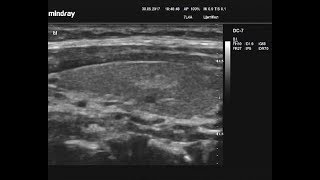

–í–ł–ī–Ķ–ĺ–∑–į–Ņ–ł—Ā—Ć –£–ó–ė –°–ī.Ű.4 4/tbŰ.JŰ`Ű Ű t. ňJ’�TźQ� Õ video

–í–ł–ī–Ķ–ĺ–∑–į–Ņ–ł—Ā—Ć –£–ó–ė - –°–ĺ–Ľ–ł–ī–Ĺ—č–Ļ —É–∑–Ķ–Ľ - TIRADS 4

–í–ł–ī–Ķ–ĺ–∑–į–Ņ–ł—Ā—Ć –£–ó–ė - –°–ĺ–Ľ–ł–ī–Ĺ—č–Ļ —É–∑–Ķ–Ľ - TIRADS 4 –í–ł–ī–Ķ–ĺ–∑–į–Ņ–ł—Ā—Ć –£–ó–ė - –°–ĺ–Ľ–ł–ī–Ĺ—č–Ļ —É–∑–Ķ–Ľ - TIRADS 4

–í–ł–ī–Ķ–ĺ–∑–į–Ņ–ł—Ā—Ć –£–ó–ė - –°–ĺ–Ľ–ł–ī–Ĺ—č–Ļ —É–∑–Ķ–Ľ - TIRADS 4

–í–ł–ī–Ķ–ĺ–∑–į–Ņ–ł—Ā—Ć –£–ó–ė - –°–ĺ–Ľ–ł–ī–Ĺ—č–Ļ —É–∑–Ķ–Ľ - TIRADS 4 –í–ł–ī–Ķ–ĺ–∑–į–Ņ–ł—Ā—Ć –£–ó–ė - –°–ĺ–Ľ–ł–ī–Ĺ—č–Ļ —É–∑–Ķ–Ľ - TIRADS 4